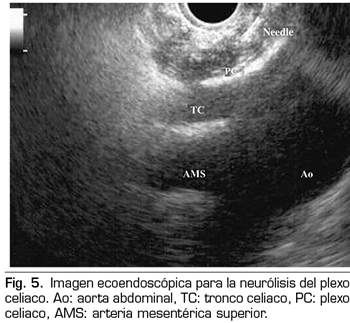

NEURÓLISIS ECOENDOSCÓPICA DEL PLEXO CELIACO

La ecoendoscopia ofrece la ventaja de una mayor visualización del plexo celiaco a corta proximidad, permitiendo una mayor precisión y seguridad en la administración del agente neurolítico y evitando la inyección en estructuras vasculares mediante el uso del Doppler (37) (Figura 5). No obstante, los trabajos que apoyan la neurólisis ecoendoscópica, considerada al igual que la técnica percutánea como una terapia de rescate, están limitados a estudios retrospectivos no controlados (38). Pauli y cols. publicaron un metanálisis que concluye que esta técnica consigue una reducción del dolor del 80 % en pacientes con cáncer de páncreas (39). Algunos estudios muestran un ligero descenso en el consumo de opioides, pero sin una fuerte evidencia científica.